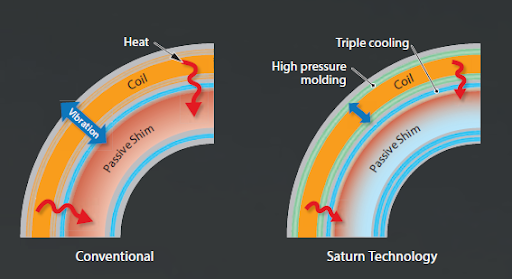

Система обладает новой высокой производительностью Saturn X Gradient.

Ее особенности:

- Амплитуда 45 мТл/м

- Скорость нарастания 200 т/м/с

- Усовершенствованный дизайн градиента

- Градиентное литье под высоким давлением

- Градиент тройного охлаждения

Технология Saturn

Технология Saturn от Canon Medical Systems обеспечивает более стабильное качество изображения благодаря повышенной стабильности градиента и точному контролю центральной частоты.